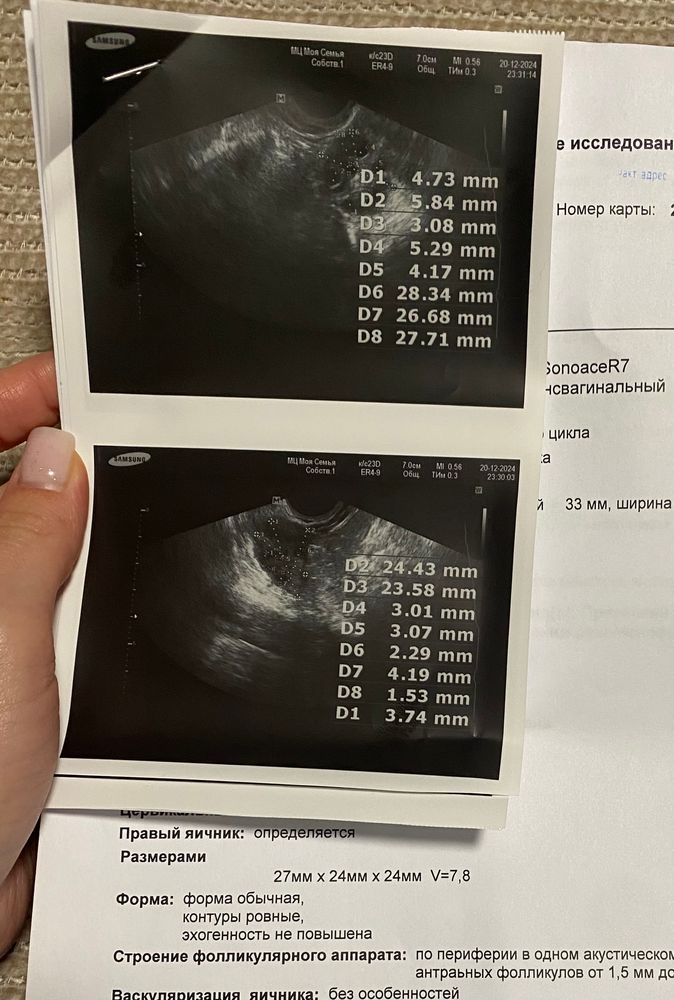

Lady blondy, МФЯ Изображение Изображение Изображение